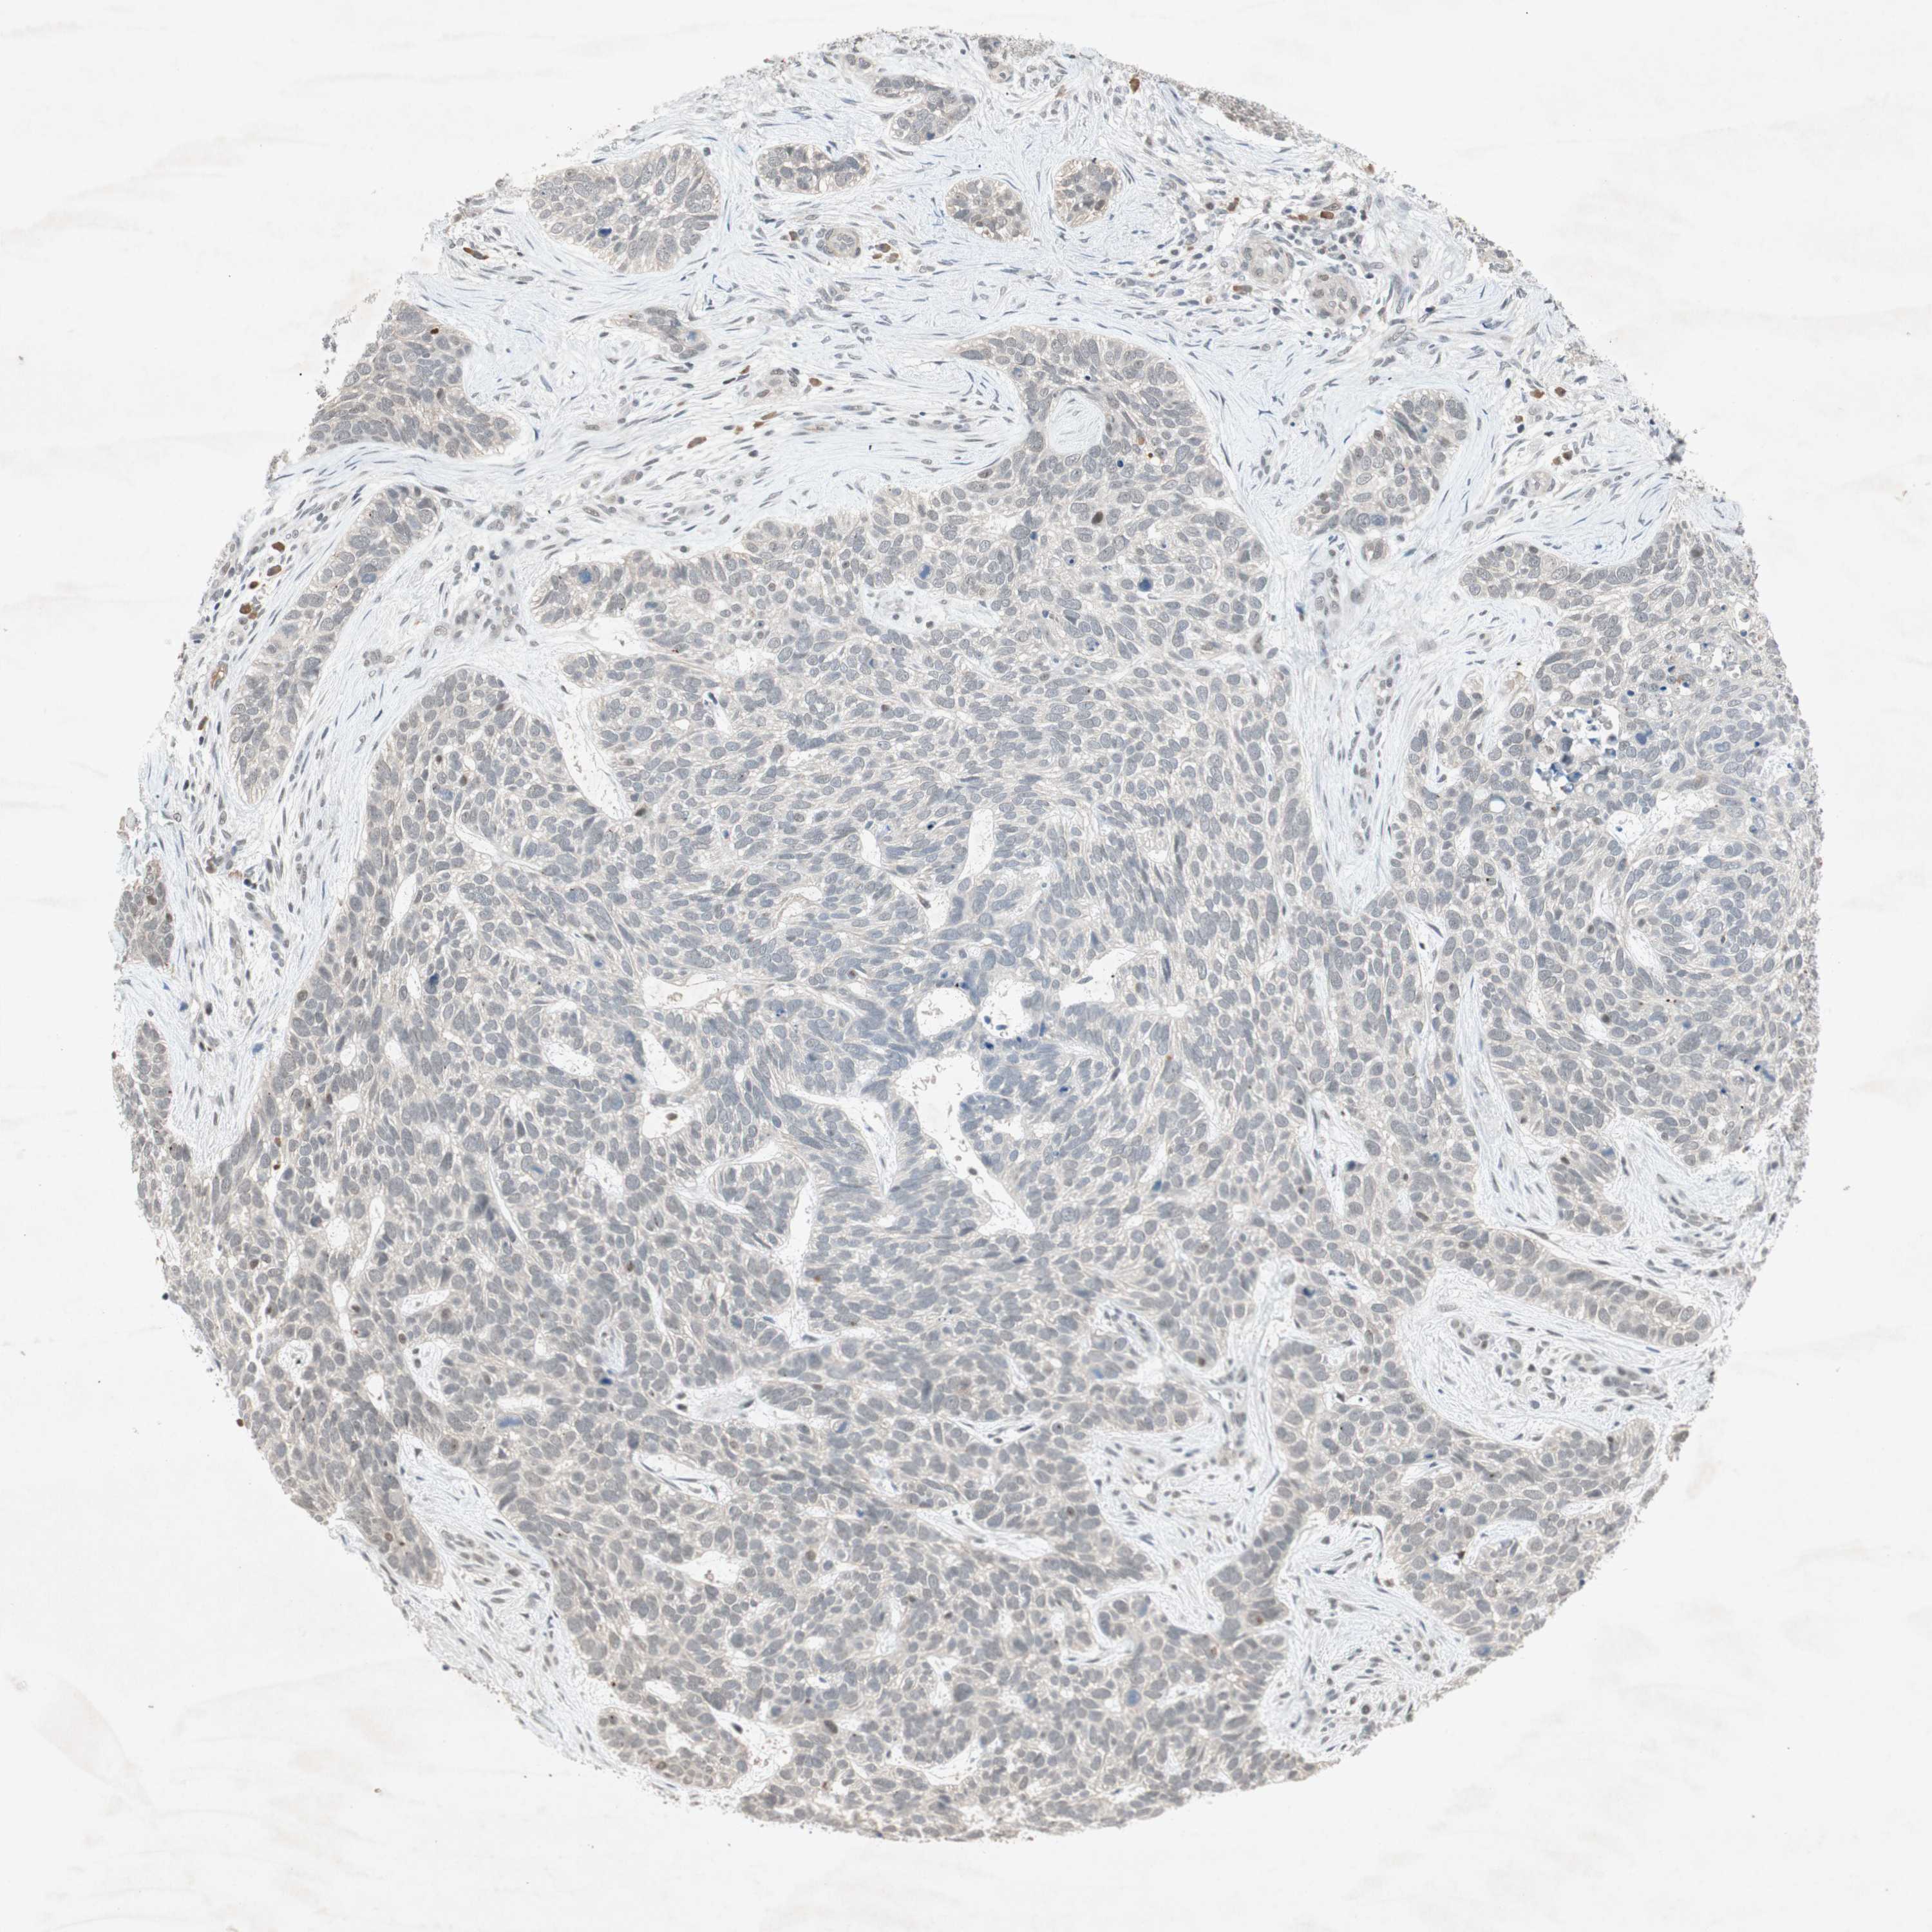

SKIN CANCER - Protein expressioni

A mouse-over function shows sample information and annotation data. Click on an image to view it in a full screen mode. Samples can be filtered based on level of antibody staining by selecting one or several of the following categories: high, medium, low and not detected. The assay and annotation is described here.

Antibody stainingi

Antibody staining in the annotated cell types in the current human tissue is reported as not detected, low, medium, or high, based on conventional immunohistochemistry profiling in selected tissues. This score is based on the combination of the staining intensity and fraction of stained cells.

Each image is clickable and will lead to virtual microscopy that enables deeper exploration of all samples and also displays staining intensity scores, fraction scores and subcellular localization as well as patient and tissue information for each sample.

Antibody HPA003750

Staining

High

Medium

Low

Not detected

Intensity

Strong

Moderate

Weak

Negative

Quantity

>75%

75%-25%

<25%

None

Location

Nuclear

Cytoplasmic/membranous

Cytoplasmic/membranous,nuclear

Squamous cell carcinoma, NOS

Squamous cell carcinoma, metastatic, NOS

Basal cell carcinoma

Papilloma, NOS